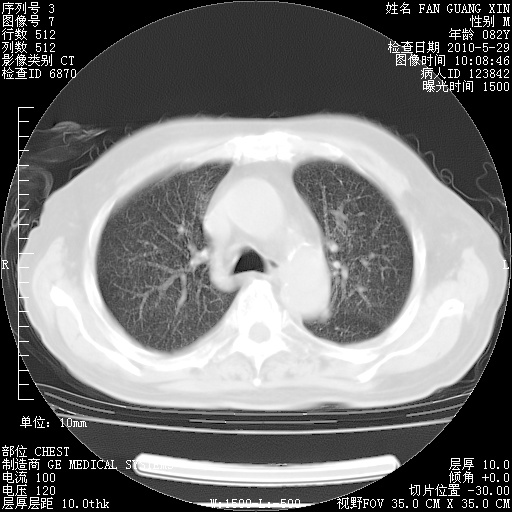

再治疗10天后的肺部CT

再治疗10天后的肺部CT 纵膈窗

肺部体征:呼吸25次/分,心率100次/分,呼吸音增粗。无干湿罗音。

血常规:15.36×10 [sup]9[/sup]/L  N0.92  L0.036  M0.045 ESR 27mm/h。

血生化:白蛋白33.30g/L  球蛋白23.67g/L  CRP 32.82mg/L 肝肾功能正常。电解质正常。

从白细胞总数和中性比例看好像合并感染。肺部纹理好像比上次多,支气管炎?其他感染?

阅读此次胸部CT,肺间质渗出性改变较入院时有吸收。目前从体温、白细胞、中性分叶明显增高,肯定存在细菌感染(发生医院感染哦,若无消化道及泌尿系统等感染的依据,肺部感染可能大)。若你院头孢哌酮舒巴坦钠耐药率较高,同意你的方案,若48小时体温仍高,可考虑使用碳青霉稀类抗菌药物,同时可予超声雾化、注意滴数时加大液体量。白蛋白33.30g/L较低哦,需加强营养等支持治疗。